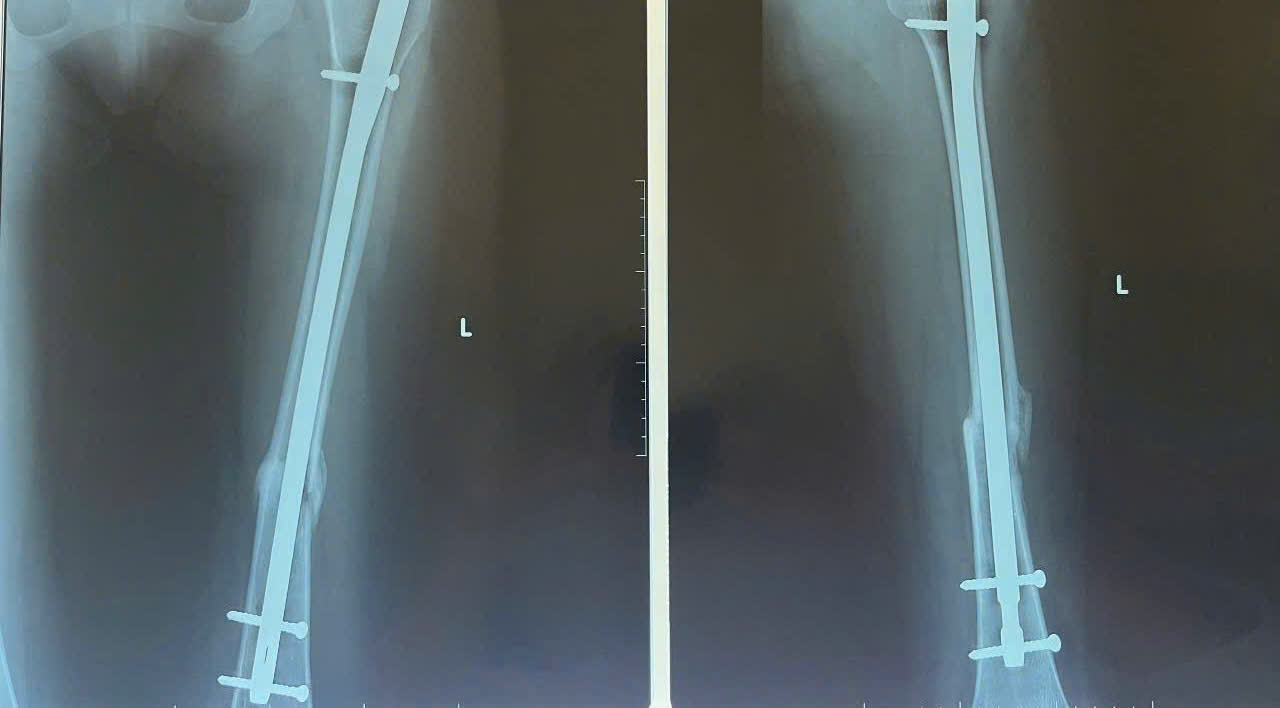

PHƯƠNG PHÁP ĐÓNG ĐINH NỘI TỦY KHÔNG MỞ Ổ GÃY TRONG ĐIỀU TRỊ GÃY KÍN XƯƠNG ĐÙI

Khoa Ngoại Chấn thương chỉnh hình – Bỏng, Bệnh viện đa khoa tỉnh Quảng Ngãi đã phẫu thuật thành công liên tiếp nhiều ca gãy kín xương đùi bằng kỹ thuật đóng đinh nội tủy xương đùi có chốt với đường mổ nhỏ không mở ổ gãy (kỹ thuật đóng đinh nội tủy). Đây là kỹ thuật được thực hiện thường quy tại BVĐK tỉnh Quảng Ngãi, giúp bệnh nhân hoà nhập lại với cuộc sống sinh hoạt hằng ngày.